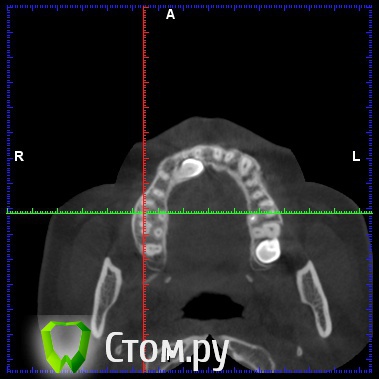

diesel87 Опубликовано 19 декабря, 2013 Поделиться Опубликовано 19 декабря, 2013 Обратилась пациентка, ретенированный 13, располагается горизонтально, брекет систему ставить не хочет, просит удалить этот клык и поставить на его место имплантат, меня интересует вот что, клык то я удалю, что с последующей имплантацией и когда ее провести, просто по кт клык залегает перпендикулярно ось имплантата, прилагаю срезы кт Ссылка на комментарий

diesel87 Опубликовано 19 декабря, 2013 Автор Поделиться Опубликовано 19 декабря, 2013 Меня интересует, как быть с отсутствием кости после удаления, размером с клык, если сразу то есть около 7 мм по вертикали, а потом провал в 4,5 мм и снова кость Ссылка на комментарий

diesel87 Опубликовано 5 января, 2014 Автор Поделиться Опубликовано 5 января, 2014 Планирую удаление, сразу графт и походу может быть винт,хотел по размеру винта проконсультироваться, по КТ расстояние от 14 до 12 зубов 7,2 мм а по вестибулярно-щечному 5,42, с небной стороны не большой провал из-за небного положения клыка, и по длине интересует 12 или 14 ми, планирую 3,8 на 12. Ссылка на комментарий